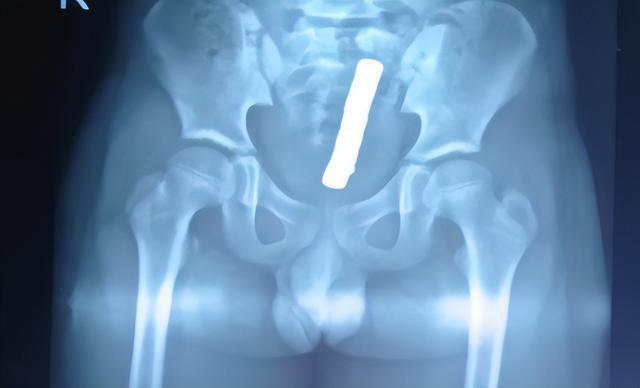

起初,家长并未察觉异常,直到小颖出现持续腹痛、腹胀等不适,使用开塞露通便后仅排出5颗磁力珠,剩余3颗滞留体内。家人紧急送医,经检查确诊为直肠穿孔,情况十分危急。

手术中,医生发现小颖肠道存在多处穿孔,随即为其实施直肠修补术+乙状结肠造口术+内镜下直肠内异物去除术。

(▲术中从直肠取出的磁力珠)

医生提醒,儿童误吞或误塞磁力珠,切勿自行处理。无论是否出现不适症状,一旦发现需立即送医,通过X光、CT等检查明确异物位置与数量,评估肠道损伤程度。未造成严重损伤时,可通过内镜微创取出;若已出现穿孔、梗阻,则必须紧急手术干预。